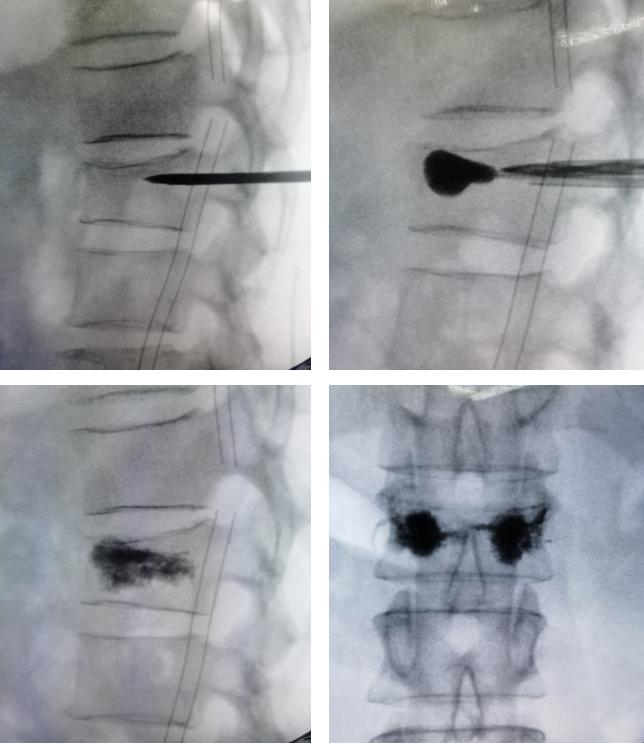

椎体成形术指经皮向骨折椎体注入骨水泥,以增加椎体强度,恢复椎体稳定,同时通过骨水泥发热来破坏痛觉神经,迅速止痛的一种微创脊柱外科手术。其优势如下:

3.X线透视定位,精准安全操作。

入院后完善检查,排除手术禁忌后,由曹主任主刀,为王阿姨行“腰1椎体新鲜压缩骨折椎体成形术”。

椎体成形术微创治疗胸腰椎压缩性骨折

术后王阿姨疼痛即刻缓解,1天后即可下床活动,配合局部理疗,舒筋通络,消炎止痛,术后1天即可出院。